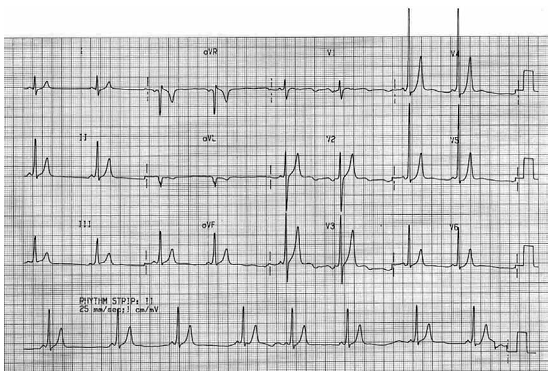

Homem, 22 anos, é trazido a serviço de emergência com taquicardia instável de QRS largo. Realizada cardioversão elétrica sincronizada. No gráfico, mostra-se o traçado de eletrocardiograma realizado após a cardioversão.

enunciado 997845-1

O diagnóstico provável é: